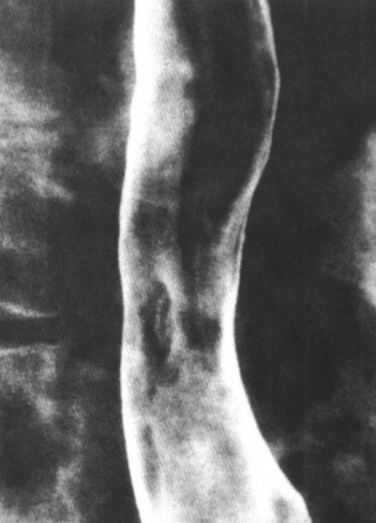

食管痉挛:螺旋状、波浪形。

食管痉挛:螺旋状、波浪状